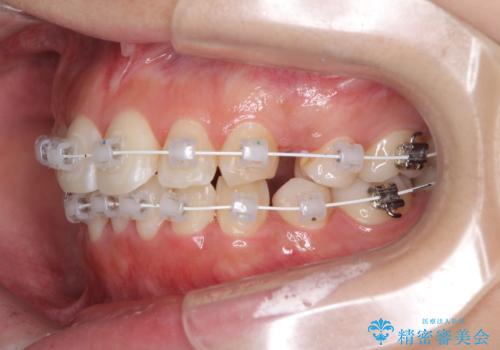

- 八重歯やデコボコをインビザラインで治療したいとのことで来院された患者様です。

インビザライン単体で治療を行うには叢生が強いと判断されたため、事前にワイヤー装置で抜歯矯正を行い、ある程度改善してからインビザラインにて仕上げていくこととしました。